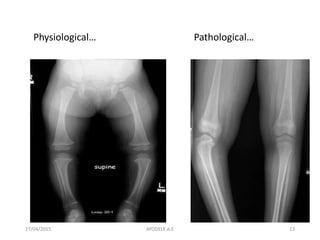

27/04/2015 13

Physiological… Pathological…

• In contrast to physiological bowing, abnormal alignment

occurs in the proximal tibia and not in the joint.